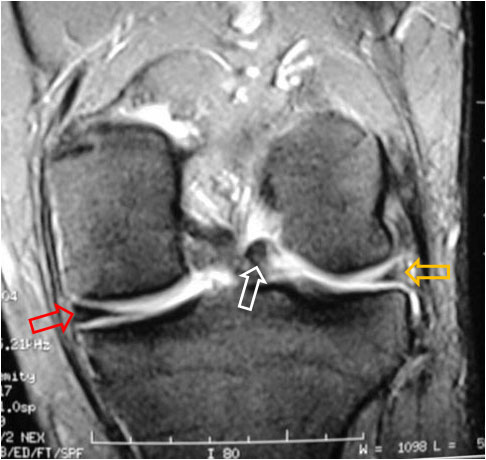

SIGNO DEL DOBLE LIGAMENTO CRUZADO POSTERIOR

Signo de rotura meniscal en los cortes sagitales de Resonancia magnética. El fragmento roto (flecha blanca) se desplaza medialmente y se coloca bajo el ligamento cruzado posterior (flecha roja), dando la imagen de duplicación de éste.